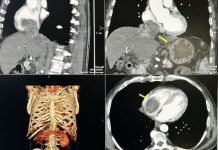

„Live surgery” директно от топ операционните на ВМА

На 28 и 29 aприл Военномедицинска академия (ВМА) ще бъде домакин на 13-ия Симпозиум „Ендоурология и минимално инвазивна хирургия”. Това е ежегодно научно събитие,...